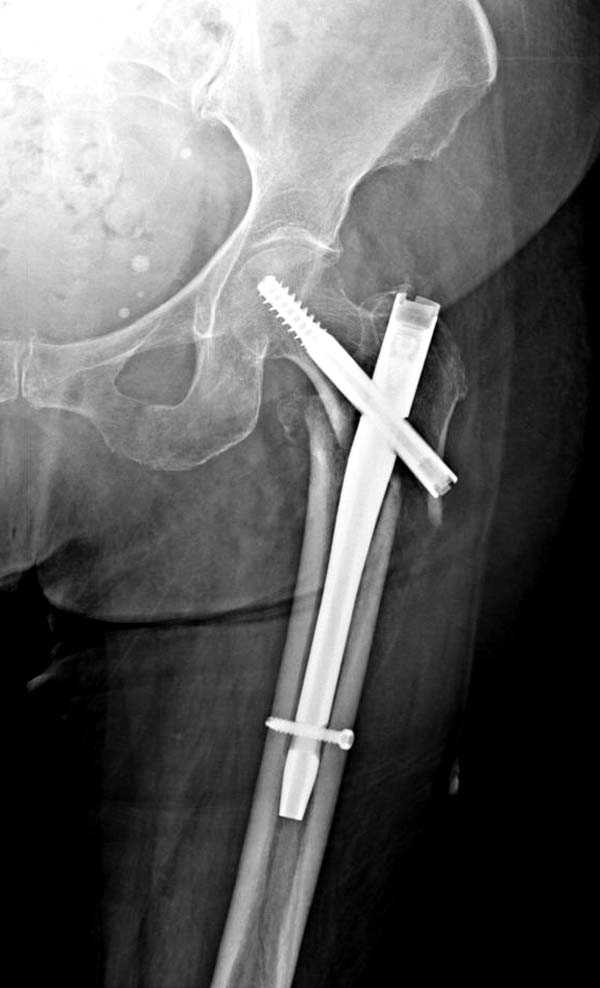

При первом послеоперационном поликлиническом осмотре больная предъявила жалобы на боли в бедре. В серийных снимках обнаружен продольный перелом верхнего отдела бедра.

Считаем, что техническая ошибка произошла во время установки гвоздя, когда рассверливанию канала не уделили должного внимания. Канал остался узковат, и гвоздь был забит с силой. Полная нагрузка конечности приостановлена на две недели, и боли в конечности изчезли. Больная начала нагрузку и перелом срастается.-- Djoldas Kuldjanov, M.D.Associate ProfessorDepartment of Orthopedic SurgerySt. Louis University

I have a different interpretation of this case. I suspect you did not tighten the set screw all the way in order to allow sliding of the lag screw and fracture fragment compression, as you would for a standard intertrochanteric hip fracture. This is a reverse obliquity fracture, so the result is migration of the proximal segment. I doubt reaming the canal would have prevented this. Had the set screw been fully tightened, there would be no postoperative fragment motion.

Мне тоже представляется, что это не единственная проблема. Продольные трещины заживают легко и быстро. Интересно, почему увеличился варус и

появилась медиализация дистального отломка.

Мне думается, что варусное положение проксимального отломка на последующих снимках не более чем проекционный феномен. Раскол же диафиза вдоль, наверняка, связан с чрезмерно насильственным введением штифта. Вообще, при реверсивных, да и обычных вертельных переломах, многие давно отказались от короткой Гаммы в пользу long-версии. Но в любом случае надо быть на 100 уверенным в подготовке канала.

Перелом А3, подвертельный, вероятно, на длинной версии гвоздя такого бы не произошло